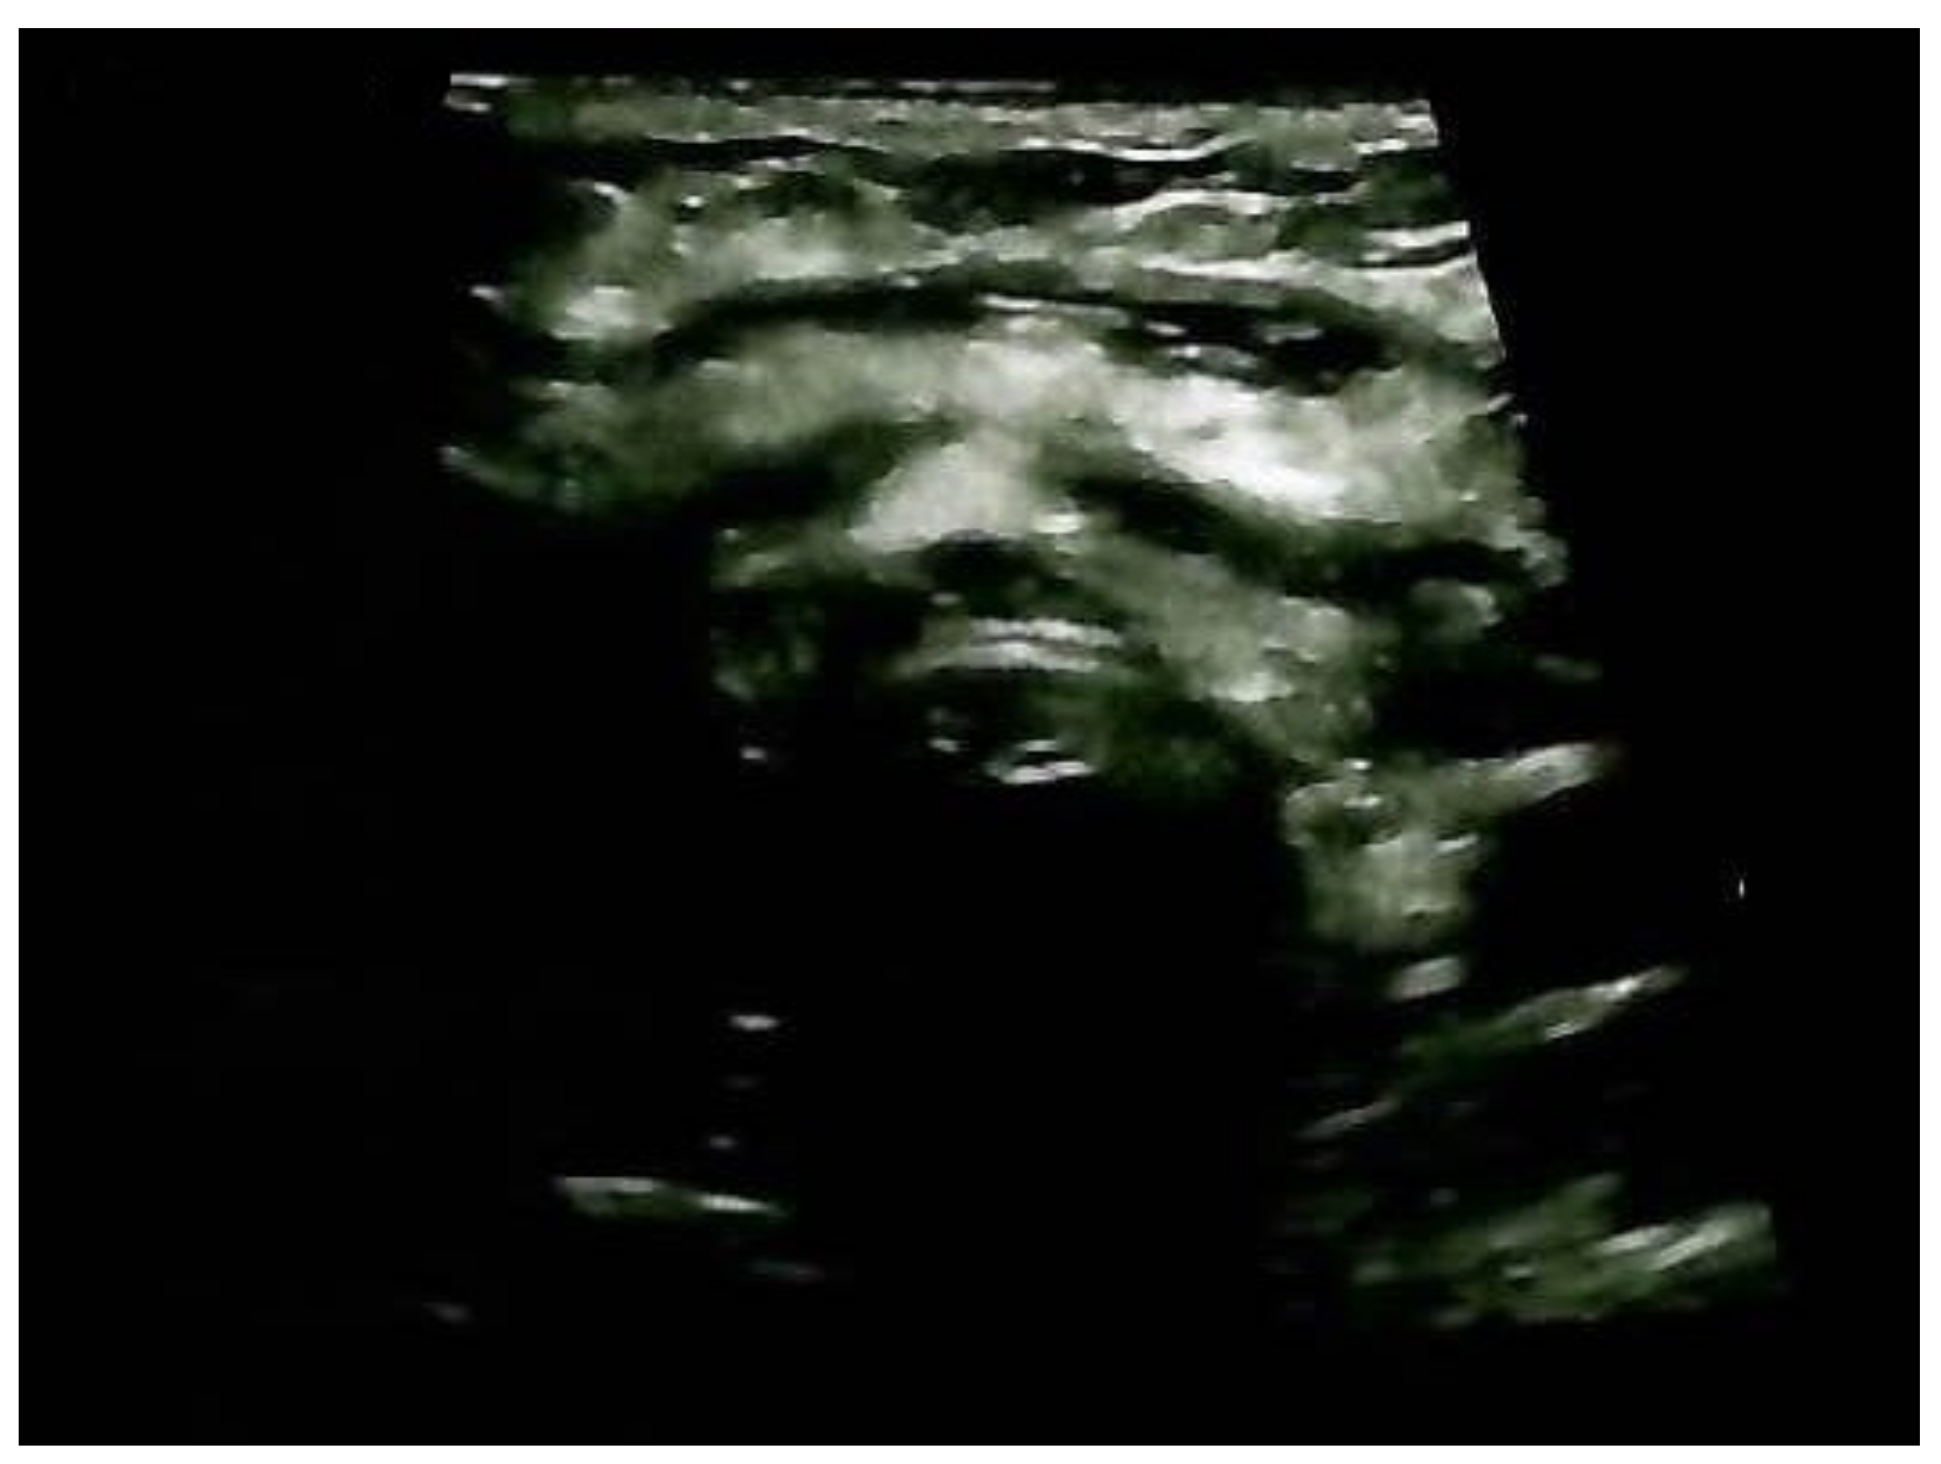

A neck ultrasound showed mild post-surgical cervical edema and no thyroid remnants (Figure 11).

Figure 11.

Anterior cervical ultrasonography after total thyroidectomy and ETTM removal: cervical edema and no thyroid tissue remnants.